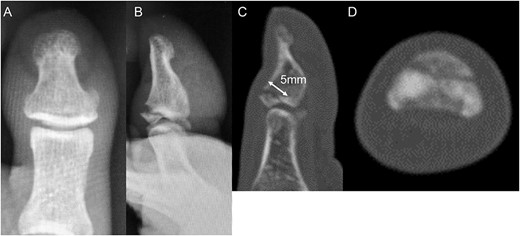

A 54-year-old man injured his right great toe while walking and wearing sandals. He complained of tenderness, swelling, and pain during motion. He could bear weight but could not actively extend the interphalangeal (IP) joint of the hallux. He was referred to our outpatient clinic 3 days after the injury. Physical examination revealed swelling, tenderness, and motion pain, and the patient could not extend the IP joint of the hallux. Plain lateral radiography and computed tomography revealed a displaced avulsion fracture of the dorsal base of the distal phalanx (Fig. 1). Surgery was performed under general anesthesia after informed consent was obtained on posttraumatic day 11. A Y-shaped incision was made at the center of the dorsal IP joint, and the displaced bony fragment was attached to the extensor hallucis longus (EHL). The IP joint was temporarily fixed with a 1.6 mm Kirschner wire, and the fragment was repositioned and fixed with two 1.5 mm cortical screws (APTUS® Hand, Medartis, Basel, Switzerland). A 4-0 FiberWire® (Arthrex, Naples, FL, USA) was fastened as an augmentation proximally to the EHL tendon and distally to the periosteum of the distal phalanx in a figure eight (Fig. 2). Postoperatively, the ankle was externally fixed in dorsiflexion from the leg to the toe, and heel loading was permitted. A total of 4 weeks after surgery, the Kirschner wire was removed to allow active motion of the IP joint of the hallux, and weight bearing was allowed on the hallux 5 weeks postoperatively. Plain radiographs taken 3 months after surgery confirmed bone healing (Fig. 3). A total of 20 months postoperatively, the patient acquired normal function, and the range of motion of the affected IP joint ranged from −3° to 30°, with no difference from the unaffected side (Fig. 4). Skin necrosis or nail deformities were not observed.

Physical findings 20 months after surgery (A) show EHL relief. Active motion shows IP joint range from (B) –3 to (C) 30°.